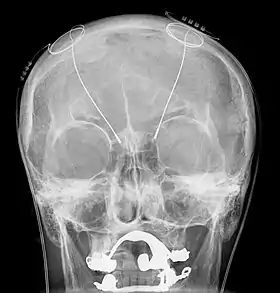

A radiography during an intervention of deep brain stimulation

Deep brain stimulation treats intention tremors, but does not help related diseases or disorders such as dyssynergia and dysmetria.[17] Deep brain stimulation involves the implantation of a device called a neurostimulator, sometimes called a "brain pacemaker". It sends electrical impulses to specific parts of the brain, changing brain activity in a controlled manner. In the case of an intention tremor, the thalamic nuclear region is targeted for treatment. This form of treatment causes reversible changes and does not cause any permanent lesions. Since it is reversible, deep brain stimulation is considered fairly safe. Reduction in tremor amplitude is almost guaranteed and sometimes resolved. Some individuals have seen sustained benefits in MS progression.[18]